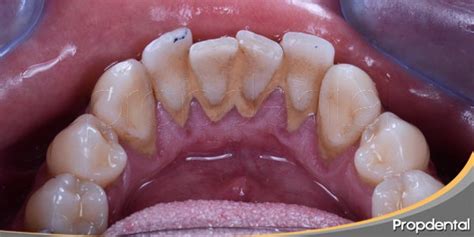

El sarro, también conocido como piedra dental, es la calcificación de la placa dental. La placa se origina a través del contacto entre la saliva y las bacterias derivadas de los alimentos. El sarro se identifica fácilmente como una pasta amarillenta o marrón que se adhiere a nuestros dientes.

La placa dental es una película blanquecina que se va depositando en la superficie dental, pero también en las encías. En un inicio, cuando la placa está blanda y no se ha solidificado formando el sarro dental o cálculo, el biofilm no es visible a simple vista. Si no eliminamos regularmente la placa inicialmente blanda cepillándonos los dientes, minerales como el calcio y el fosfato de la saliva se depositan en la biopelícula que se forma en los dientes. Esto provoca la calcificación de la placa y la formación de sarro duro.

- Sarro supragingival: Se produce por encima de la línea de las encías, preferentemente en la cara interna de los dientes frontales inferiores y en la cara externa de los molares superiores.